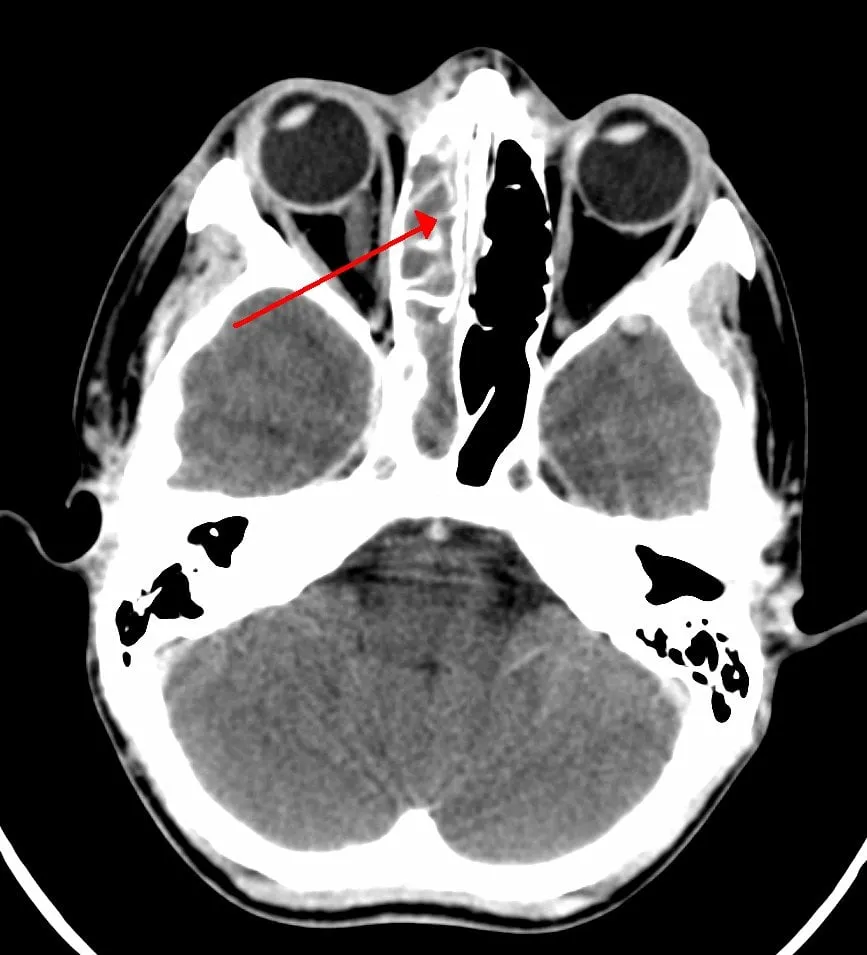

Photo : infection du sinus ethmoïdal

• La sinusite ethmoïdale entraîne des douleurs derrière et entre les yeux et des maux de têtes frontaux (souvent décrites comme atroces) au niveau du front.

• une tomodensitométrie (TDM) peut déterminer l’étendue et la sévérité de la sinusite.